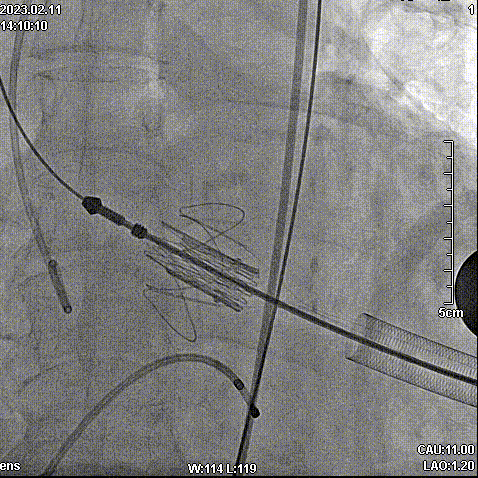

2月11日,新疆维吾尔自治区人民医院杨毅宁教授团队成功应用J-Valve完成两例具有挑战性的横位心TAVR病例。其中一例为窦部扩张+横位心,另外一例为升主动脉增宽+横位心,且两例患者均为主动脉瓣关闭不全(反流)。

病例一:窦部扩张与横位心

手术步骤

拔除股动脉血管鞘,缝合股动脉。手术顺利结束。